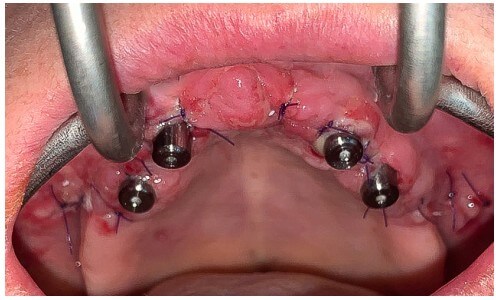

Paciente con edentulismo completo y reabsorción avanzada en maxilar superior.

Rechaza opción removible.

Se planifica rehabilitación completa con 4 implantes Zygoma.

Planificación 3D y confección de férulas quirúrgicas para abordaje guiado.

Se colocan 4 implantes Zygoma según planificación 3D guiada bajo sedación IV, Carga inmediata a las 24 horas.

La paciente fue rehabilitada de forma definitiva a los tres de meses en su clínica origen.